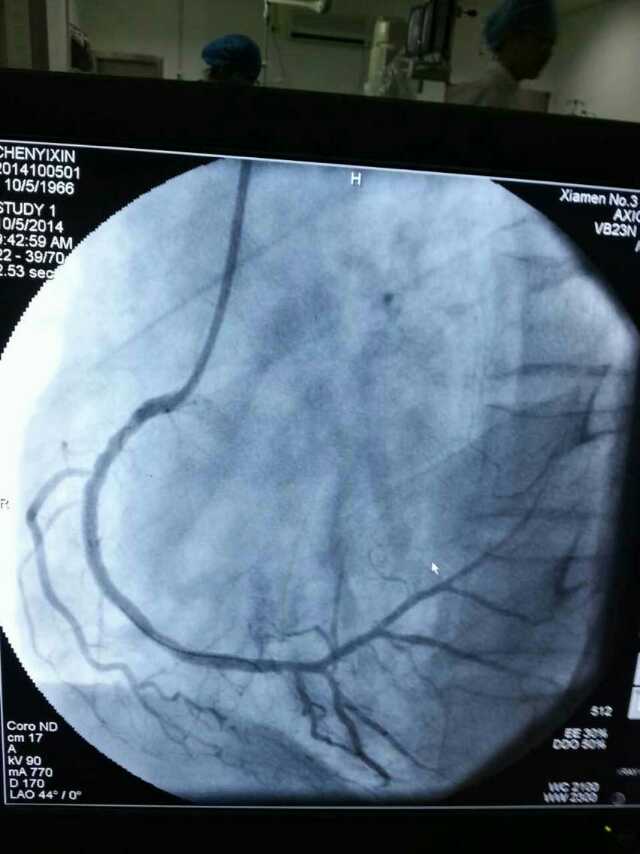

3月20日,家住翔安的庄先生为感谢伦理片 心血管内科的医护人员在第一时间对他的病情给予明确诊断,并及时采取有效治疗措施,让他的心脏病很快得到康复回家。特地送来一面写着“德医双馨,妙手回春”锦旗以表达他们满满的感激之情。